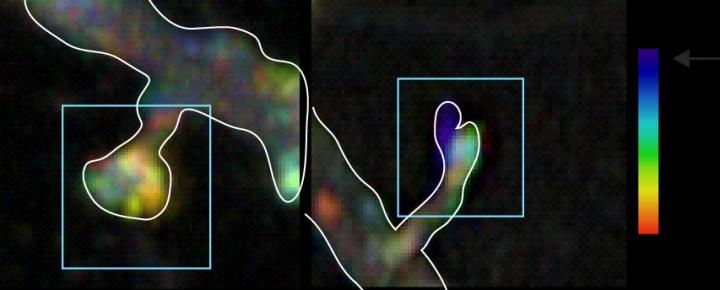

image: Blocking activation of the JNK protein in synapses stops synapses from retracting. Temporal colour coding shows that when the JNK protein is inhibited in synapses using a light beam, a structural protein called "actin" freezes in time. Changing the cells cytoskeleton is part of an array of molecular events that JNK triggers to destabilize synapses.

Postdoctoral Researcher Patrik Hollós and colleagues used a light-activated optogenetic tool to switch off the activity of a protein called JNK specifically in synapses.

- Using a light beam to inhibit the JNK protein prevented synapses from shrinking in response to stress. Specifically the internalisation of a receptor called "AMPAR", an early event in synapse disassembly, was blocked, explains Hollós.